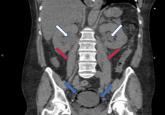

ArticleEmphysematous cystitisAuthor:Sammy Nassri, MDPublish date: January 3, 2019The patient had fallen in her home and remained on the floor for 2 days until neighbors heard her cries and called 911.Read More